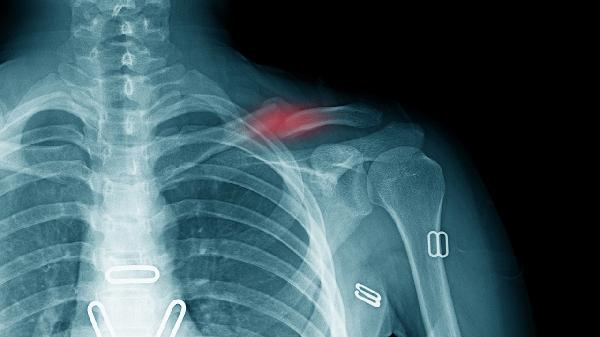

肩部直接撞击、跌倒时手臂撑地或运动损伤可能导致锁骨骨膜、周围韧带或肌肉拉伤,甚至锁骨骨折。疼痛通常急性发作,伴有局部肿胀、瘀斑,关节活动受限。急性期应立即休息、冰敷患处,使用绷带或吊带固定制动以减少进一步损伤。若疼痛剧烈或怀疑骨折,须及时就医进行X光检查。

暴力外伤是锁骨骨折主因,骨折端移位可能刺激周围神经血管,引起剧烈疼痛、畸形和骨摩擦感。确诊需X光或CT检查。无移位骨折可用锁骨带固定4-6周;移位明显或开放性骨折需手术复位,如钢板内固定术,术后配合渐进式康复训练恢复关节功能。